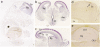

We conducted a genome-wide association study (GWAS) and a follow-up study of bipolar disorder (BD), a common neuropsychiatric disorder. In the GWAS, we investigated 499,494 autosomal and 12,484 X-chromosomal SNPs in 682 patients with BD and in 1300 controls. In the first follow-up step, we tested the most significant 48 SNPs in 1729 patients with BD and in 2313 controls. Eight SNPs showed nominally significant association with BD and were introduced to a meta-analysis of the GWAS and the first follow-up samples. Genetic variation in the neurocan gene (NCAN) showed genome-wide significant association with BD in 2411 patients and 3613 controls (rs1064395, p = 3.02 × 10(-8); odds ratio = 1.31). In a second follow-up step, we replicated this finding in independent samples of BD, totaling 6030 patients and 31,749 controls (p = 2.74 × 10(-4); odds ratio = 1.12). The combined analysis of all study samples yielded a p value of 2.14 × 10(-9) (odds ratio = 1.17). Our results provide evidence that rs1064395 is a common risk factor for BD. NCAN encodes neurocan, an extracellular matrix glycoprotein, which is thought to be involved in cell adhesion and migration. We found that expression in mice is localized within cortical and hippocampal areas. These areas are involved in cognition and emotion regulation and have previously been implicated in BD by neuropsychological, neuroimaging, and postmortem studies.